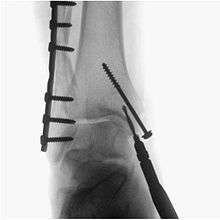

A fluoroscopy X-ray machine is a great asset during surgery for implants